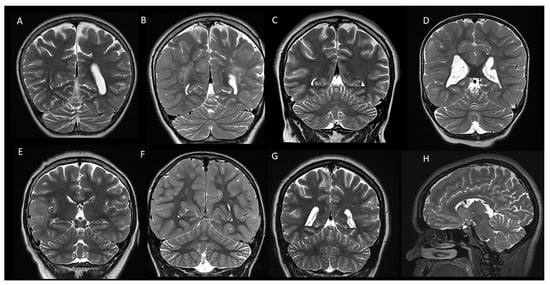

Incidence and Characteristics of Cerebellar Atrophy/Volume Loss in Children with Confirmed Diagnosis of Tuberous Sclerosis Complex

Mertiri, L.; Boltshauser, E.; Kralik, S.F.; Desai, N.K.; Lequin, M.H.; Huisman, T.A.G.M. Incidence and Characteristics of Cerebellar Atrophy/Volume Loss in Children with Confirmed Diagnosis of Tuberous Sclerosis Complex. Children 2024, 11, 627. https://doi.org/10.3390/children11060627